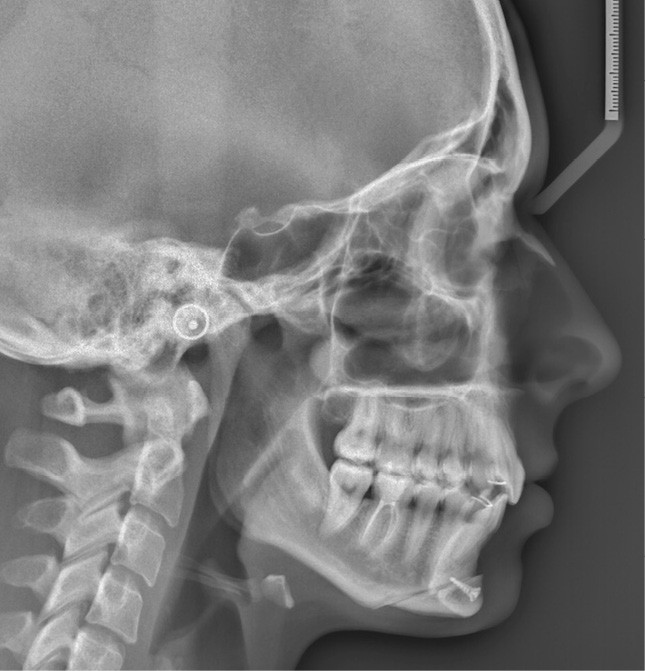

Examens complémentaires (fig. 3a,b)

À la radiographie panoramique, 31 présente une importante image apicale, confirmée par une radiographie rétroalvéolaire et également visible sur la téléradiographie de profil.

Cette dernière montre un schéma squelettique de Classe I et une typologie verticale normodivergente. Les rapports incisifs sont normaux et l’épaisseur des tissus mentonniers est insuffisante pour obtenir la fermeture buccale sans contraction. La symphyse est fine et l’incisive est centrée sur celle-ci.